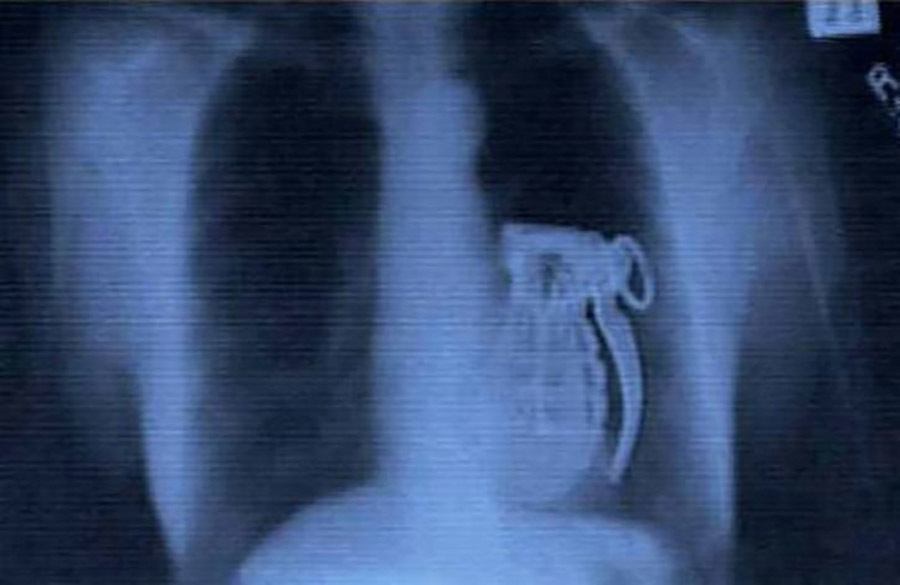

This grenade is live, reportedly swallowed by a terrorist who realized too late that the grenade couldn’t be detonated from inside a stomach.